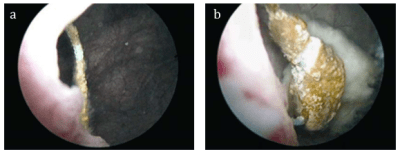

![]() |

| Dos ejemplos de cuerpo extraño. a) sutura de procedencia quirúrgica ginecológica y b) catéter ureteral calcificado. |